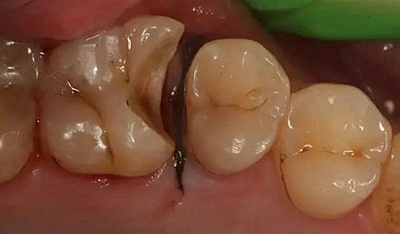

患者男性,35歲,B6銀汞充填后食物嵌塞,要求重新充填,口內(nèi)檢查見B6近中鄰頜面銀汞充填物,局部缺損,有繼發(fā)齲,去除原充填物及繼發(fā)齲,發(fā)現(xiàn)齲壞位于牙齦下方,給予冠延長(zhǎng)手術(shù),同期嵌體預(yù)備,后一次性取模。(同樣設(shè)計(jì)為齦上邊緣)

硅橡膠取模后,灌注模型,科爾琥珀樹脂制作嵌體。

一周后拆線,口內(nèi)試戴合適,粘結(jié)嵌體。